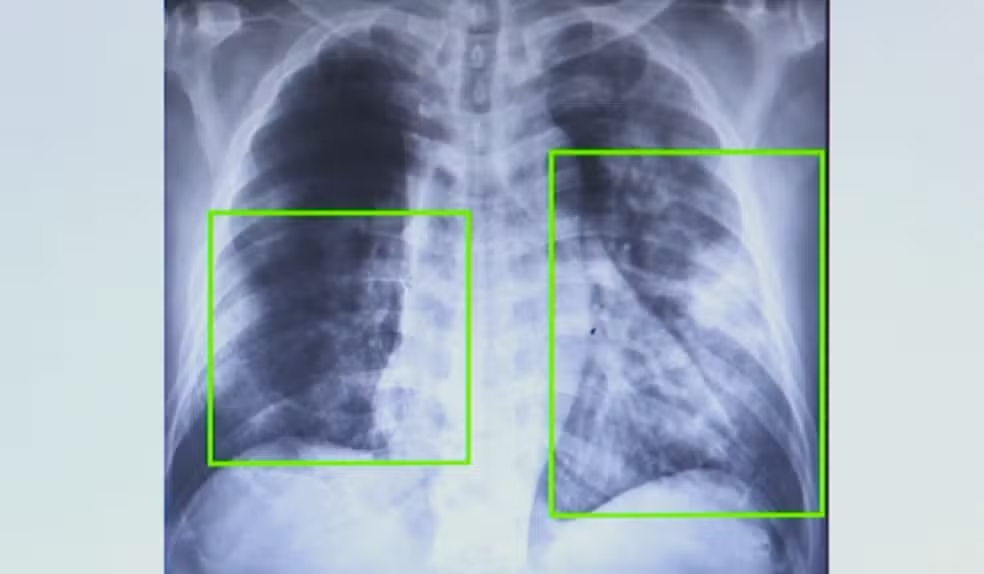

/i.s3.glbimg.com/v1/AUTH_59edd422c0c84a879bd37670ae4f538a/internal_photos/bs/2025/w/h/wH11UESdmfwtLhVFM50g/1.png)

Atendimentos por pneumonia quase dobram em 7 meses na região de Campinas. — Foto: Reprodução EPTV